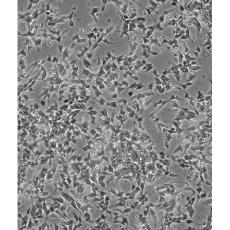

SH-SY5Y [SHSY-5Y]

產(chǎn)品名稱 SH-SY5Y [SHSY-5Y]

中文名稱 人神經(jīng)母細胞瘤細胞

組織來源 神經(jīng)母細胞瘤;骨髓來源;男性

生長特性 mixed, adherent and suspension

形態(tài)特征 epithelial-like and neuronal-like

細胞描述 SH-SY5Y cells have a reported saturation density greater than 1×10^6 cells/cm^2. They are reported to exhibit moderate levels of dopamine beta hydroxylase activity. Ref